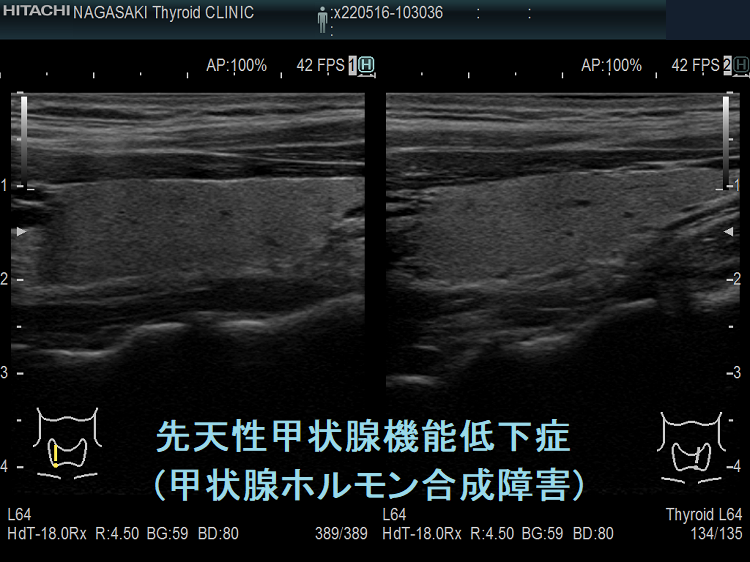

ケース①

遺伝性甲状腺ホルモン合成障害の超音波(エコー)画像は色々なパターンがあります。

- 常染色体優性遺伝型;腺腫様甲状腺腫の形態になります。

- 常染色体劣性遺伝型;新生児マススクリーニングで見つかり、適切に治療された場合、甲状腺サイズは正常、内部は低エコーで、甲状腺ホルモンをほとんど作っていないのが分かります。